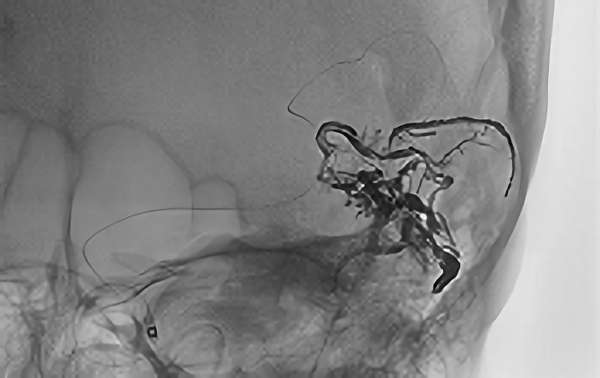

No.1600 手術前

No.1600 手術中

No.1600 手術後

'25年12月

くも膜下出血

脳底動脈瘤破裂

40代

救急外来